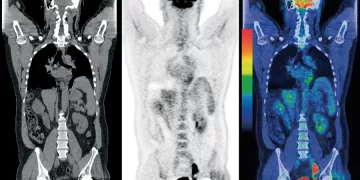

Read moreDetailsLos escáneres PET (tomografía por emisión de positrones) son una herramienta poderosa para detectar y monitorear el cáncer en el...